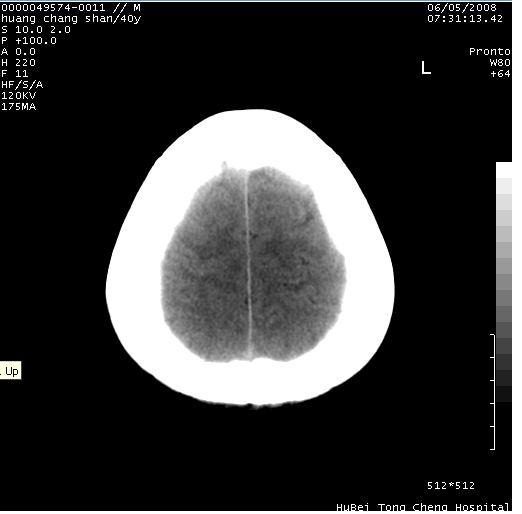

患者 m,40y。头痛,视力模糊,多饮多尿,性欲减退半年余。

行ct平扫+增强,图象如下:

平扫病灶呈等密度,增强后强化明显,均匀一致,结合病史首先考虑:垂体瘤。脑膜瘤不支持,因为脑膜瘤平扫多为实性呈均匀高密度影像,内分泌症状多不明显,垂体内分泌素测定正常。

结合临床考虑鞍上生殖细胞瘤可能性大于脑膜瘤(增强未见脑膜围征),建议结合冠状位扫描看病灶起源及垂体窝、鞍底情况。垂体窝内未见明显软组织密度影,垂体窝未见扩大,暂不考虑垂体瘤;病灶较大,未见囊变及钙化,颅咽管瘤不支持。期待结果!

2、ct表现:肿瘤呈类圆形,均匀略高密度,无囊变,无钙化。侧脑室有扩大。